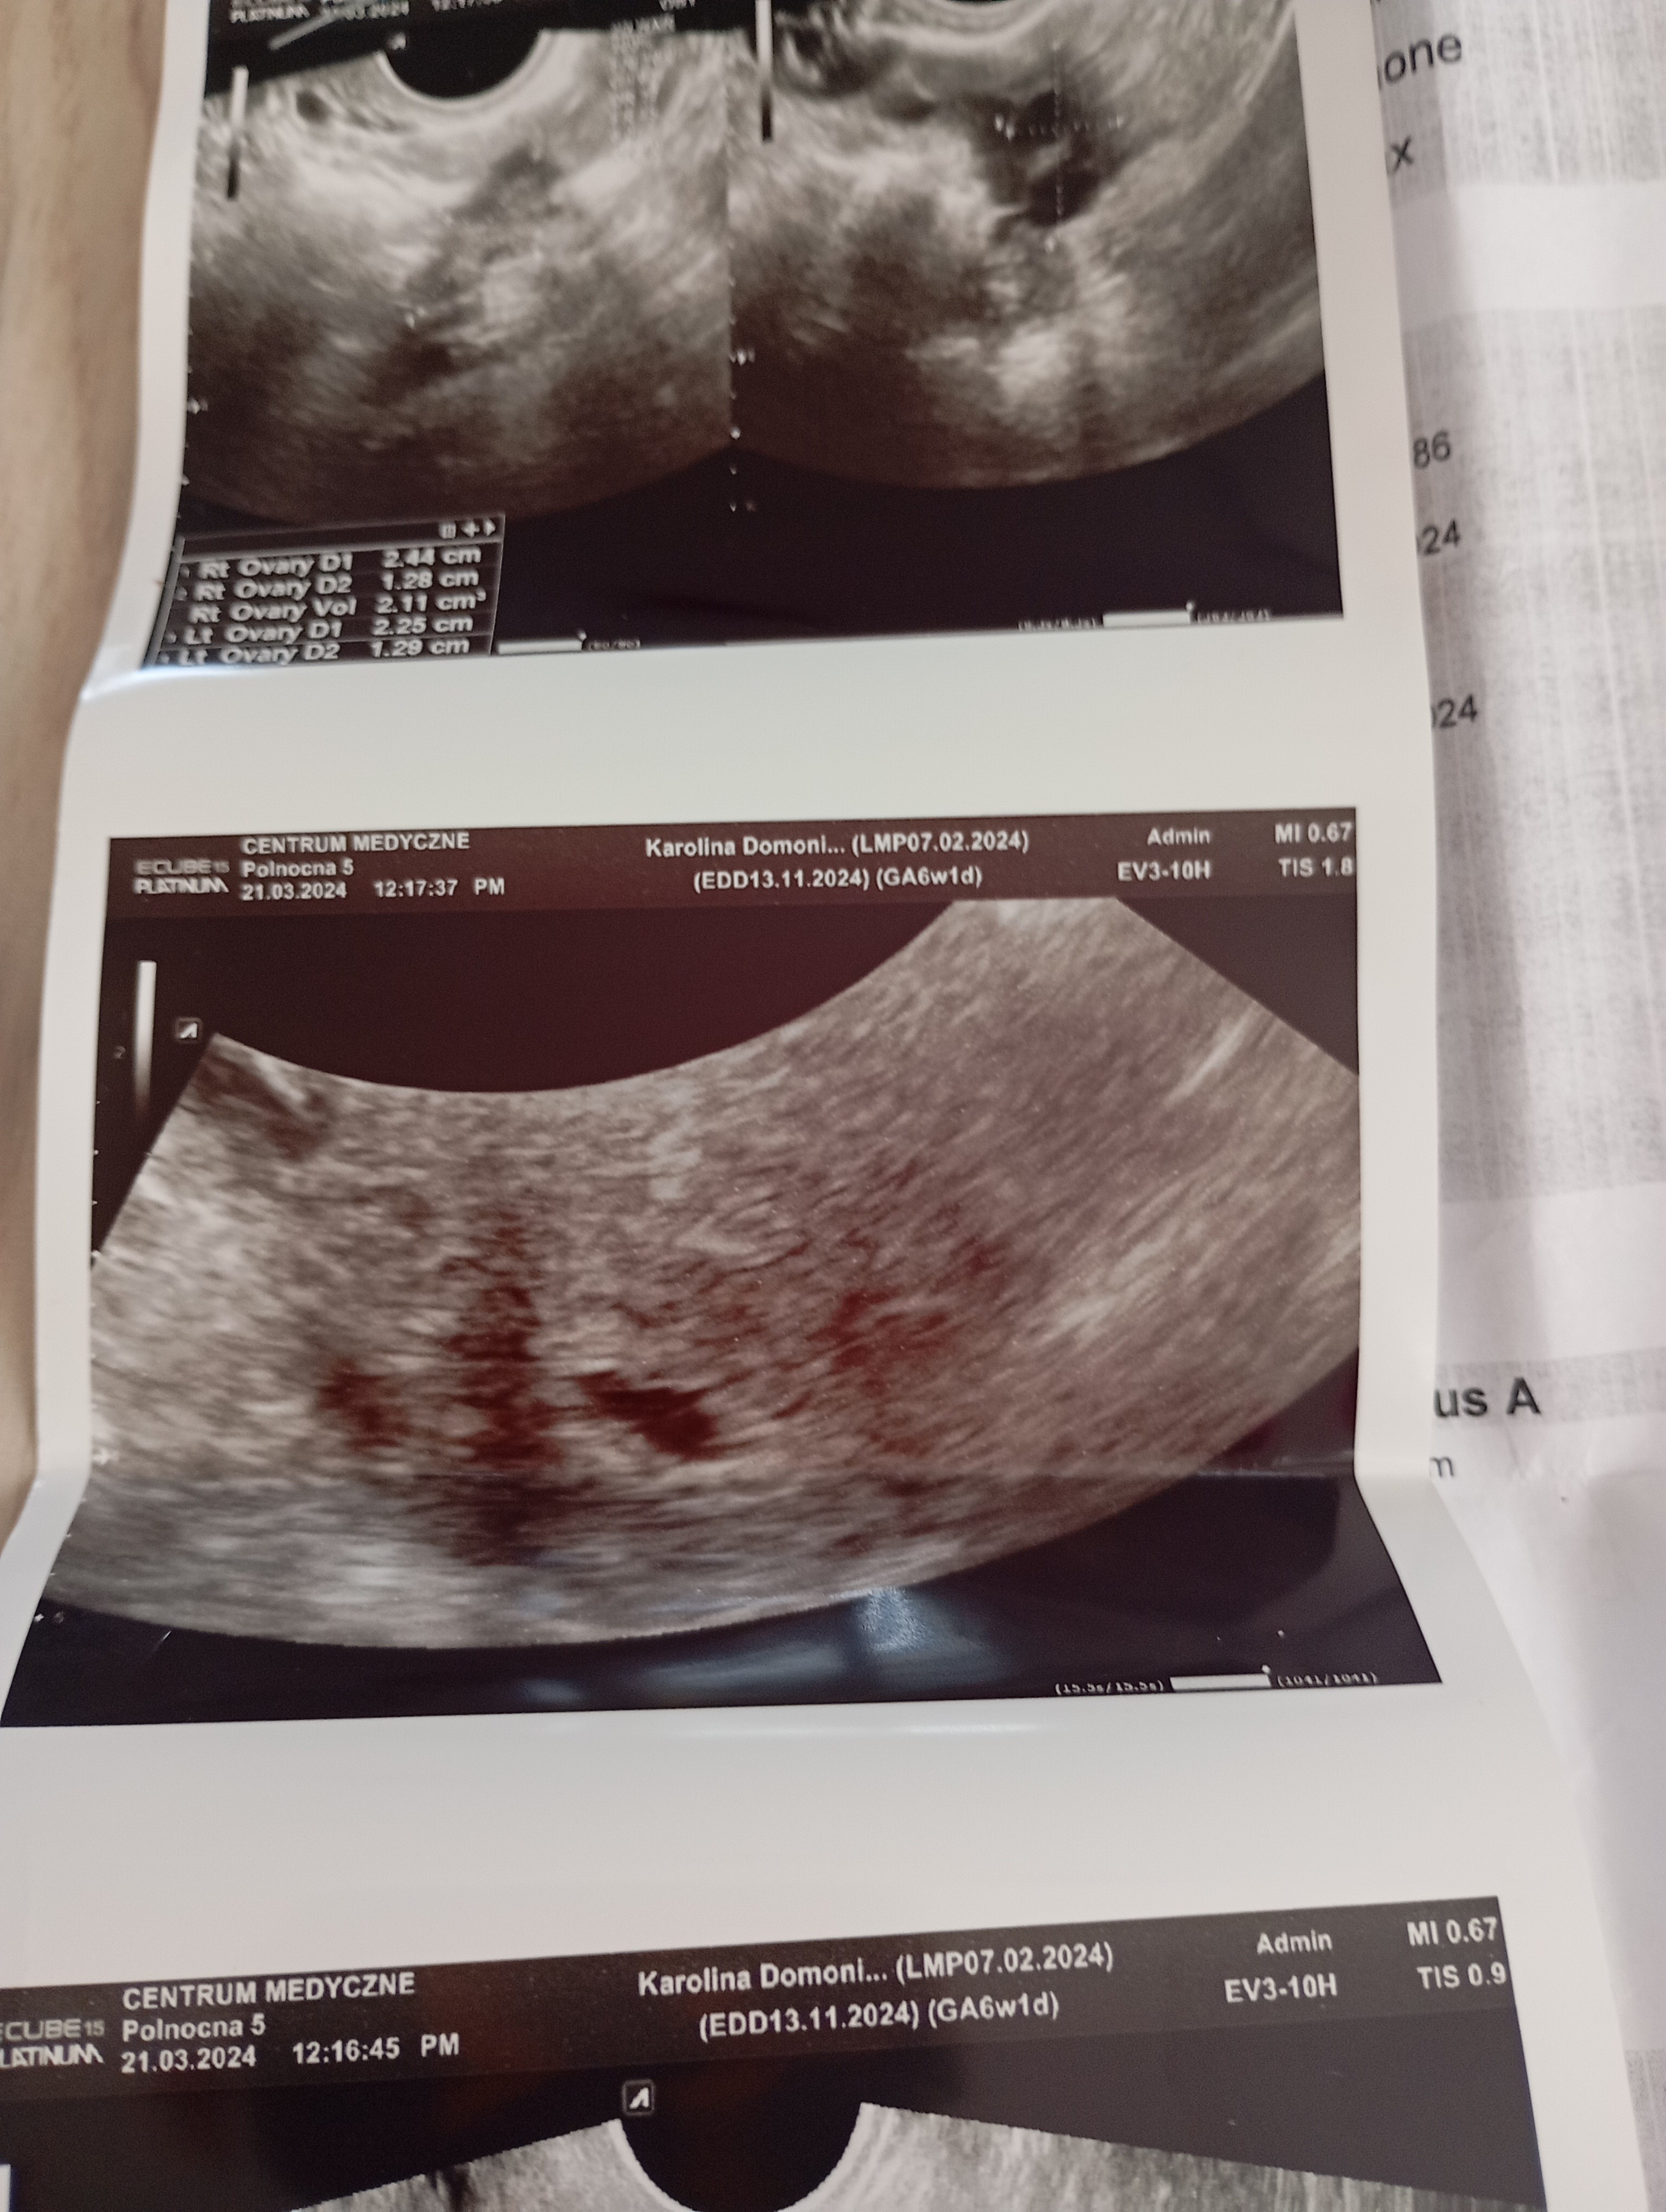

Część dziewczyny. Właśnie wróciłam od lekarza . Na USG nie widać zarodka. Strasznie nie miła lekarz nie chciała nic mówić. Kazała przyjść za tydzień i zleciła luteinę. Beta ładnie rośnie. Czy ktoś się na tym zna ?

• IMG_20240321_142521.jpg

IMG_20240321_142521.jpg

1,8 MB · Wyświetleń: 554

• IMG_20240321_142523.jpg

IMG_20240321_142523.jpg

1,8 MB · Wyświetleń: 219

• IMG_20240321_142525.jpg

IMG_20240321_142525.jpg

1,9 MB · Wyświetleń: 225